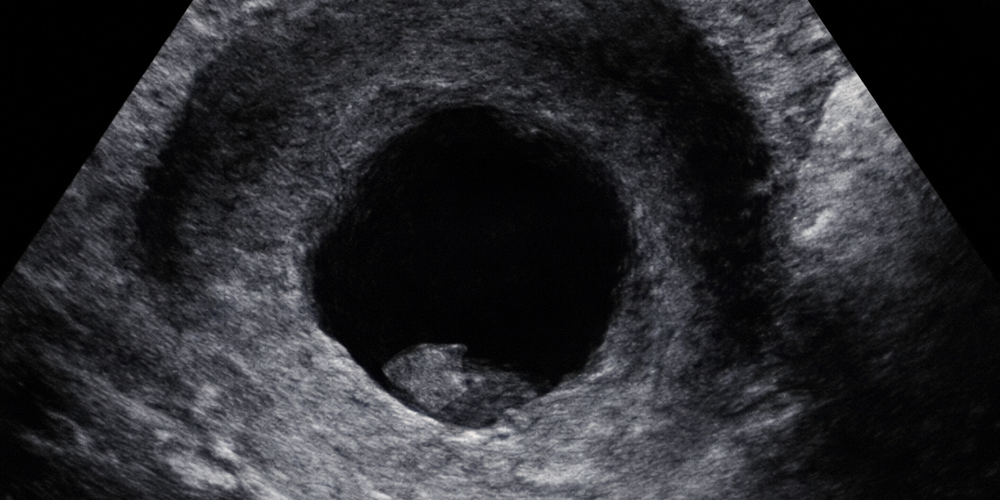

Yukarıdaki resimdeki kalbin yaşama şansının sıfır olduğu baştan belli. Kalbin sol tarafındaki karıncık hiç gelişememiş. Bu durumu anne karnında iken görebilmenin tek faydası aylar öncesinden kendilerini bekleyen acıyı aileye haber verebilmiş olmak... Bu durumda gebeliği erkenden düşükle sonlandırmak bir çözüm mü? Kişiye göre herkesin doğrusu değişir. Bana göre evet... Yapılabileceklerin en iyisi. Ama, anne-baba olarak gebeliği sonlandırma kararının sorumluluğunu ağır bulan, kabul etmeyen ve önceden belli acıları kabul edip yaşayanları da saygı ile karşılıyorum. Anne-baba olmanın ruh hali... Ben de babayım... Karışık iş...